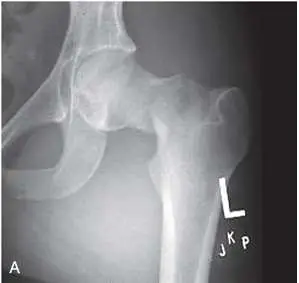

一位 25歲的年輕男性因為車禍,X 光檢查如圖所示下列敘述與處置何者最適當 ?

該 AP 投影髖關節片可見左側 femoral neck 斷裂,斷端輕度上下錯位,斷端間無 valgus impacted 特徵。構成 Shenton 線的 femoral neck inferomedial border 與 obturator foramen superior border 所連成的弧線出現明顯中斷,代表 femoral head 相對於頸部已有位移。